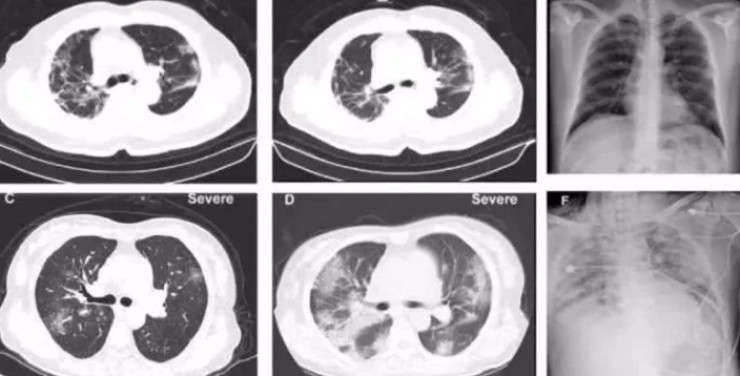

Компьютерная томография легких пациента с коронавирусной инфекцией. © Tencent News

"Мы не знаем, где находится "враг", какое "оружие" он использует для атаки и какими методами мы можем эффективно обуздать его силу. Патологоанатомическая работа похожа на "разведку". Благодаря патологической анатомии и последующим исследованиям распространение вируса в организме человека можно наблюдать под микроскопом. Можно будет понять, какие органы, ткани и клетки пострадали больше всего, в чем слабость "врага". Компьютерная томография показала появление симптомов "матового стекла" в легких пациентов", - рассказал доктор Лю Лян.